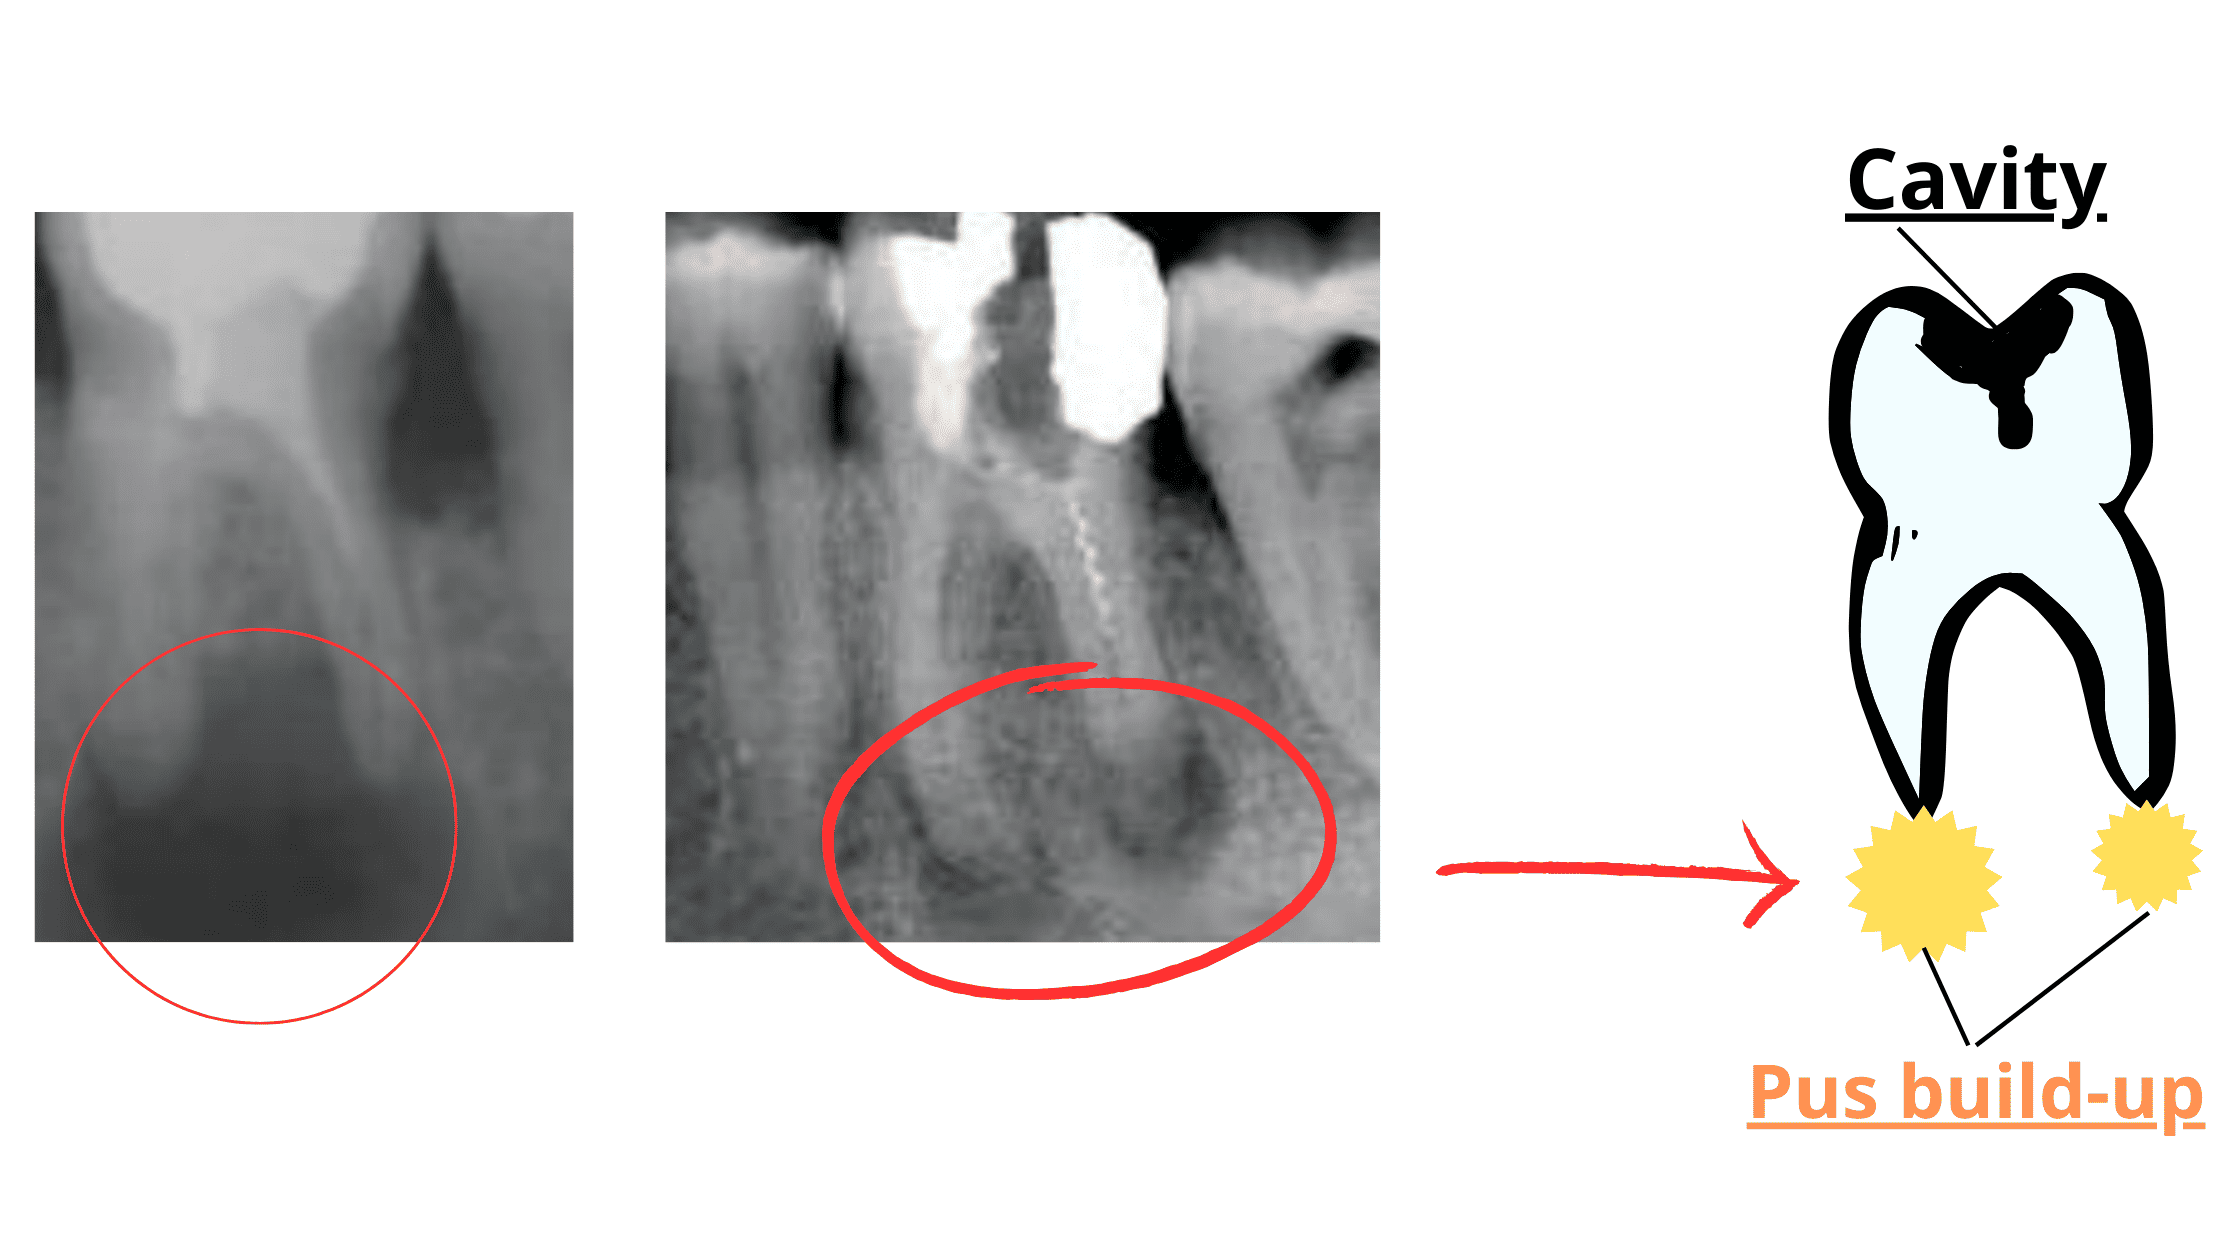

Root Canal Gone Bad Abscess . An untreated root canal fail is a dangerous infection that can lead to serious complications. How can you tell if something is wrong with your tooth after a root canal? Why do i still have an abscess despite the root canal? Root canal infections are very rare. For reinfected root canals, the most common treatment option is endodontic retreatment. Here are the most common warning signs to look for. If the abscess is still there even after the root canal (rct),. Root canal treatment involves removing the infected or damaged pulp from the inner chamber of a tooth. There are only 3 choices once an old root canal infection is diagnosed: How to tell if infection is still there. This involves reopening the tooth, removing the old root canal filling, and thoroughly cleaning and disinfecting the canals. An extremely painful abscess can result and. Learn how to recognize a root canal infection, what causes them, how to prevent them, and how they're. Retreat or redo the root canal. Do nothing and just monitor or watch the progress of the infection.